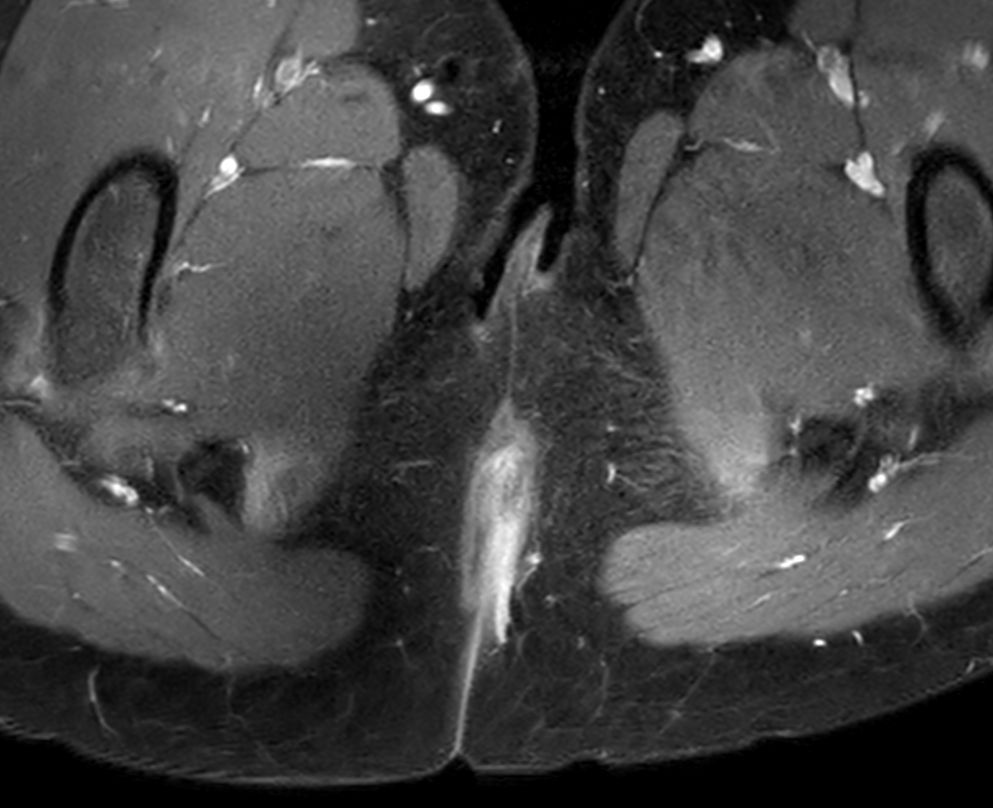

8 years old pediatric patient with a fistula in the pelvis. MultiVane XD is used to achieve high resolution diagnostic images, even in the case of severe patient motion. Integration of Compressed SENSE acceleration technique enables speeding up of the entire exam.

Axial T2w TSE Compressed SENSE